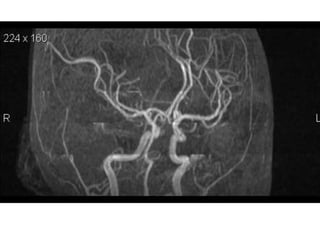

Arteries of the brain (lateral view) - MRA

1. Anterior cerebral artery

2. Anterior communicating artery

3. Basilar artery

4. branches (in insula) of middle cerebral artery

5. Cavernous portion of internal carotid artery

6. Cervical portion of internal carotid artery

7. Genu of middle cerebral artery

8. Intracranial (supraclinoid) internal carotid artery

9. Middle cerebral artery

10. Ophthalmic artery

11. Petrous portion of internal carotid artery

12. Posterior cerebral artery

13. Posterior cerebral artery in ambient cistern

14. posterior cerebral artery in interpeduncular

cistern

15. Posterior communicating artery

16. Posterior inf cerebellar artery.

17. Quadrigeminal portion of posterior cerebral

artery

18. Superior cerebellar artery

19. Vertebral artery